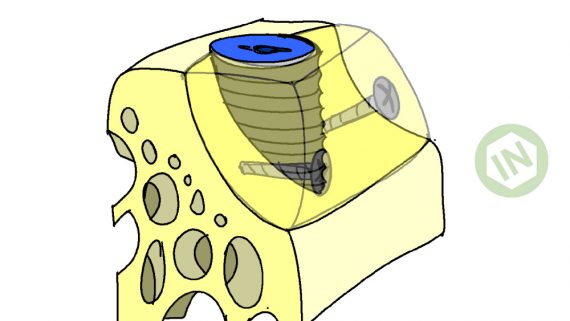

- Техника?

- Обработка лунки?